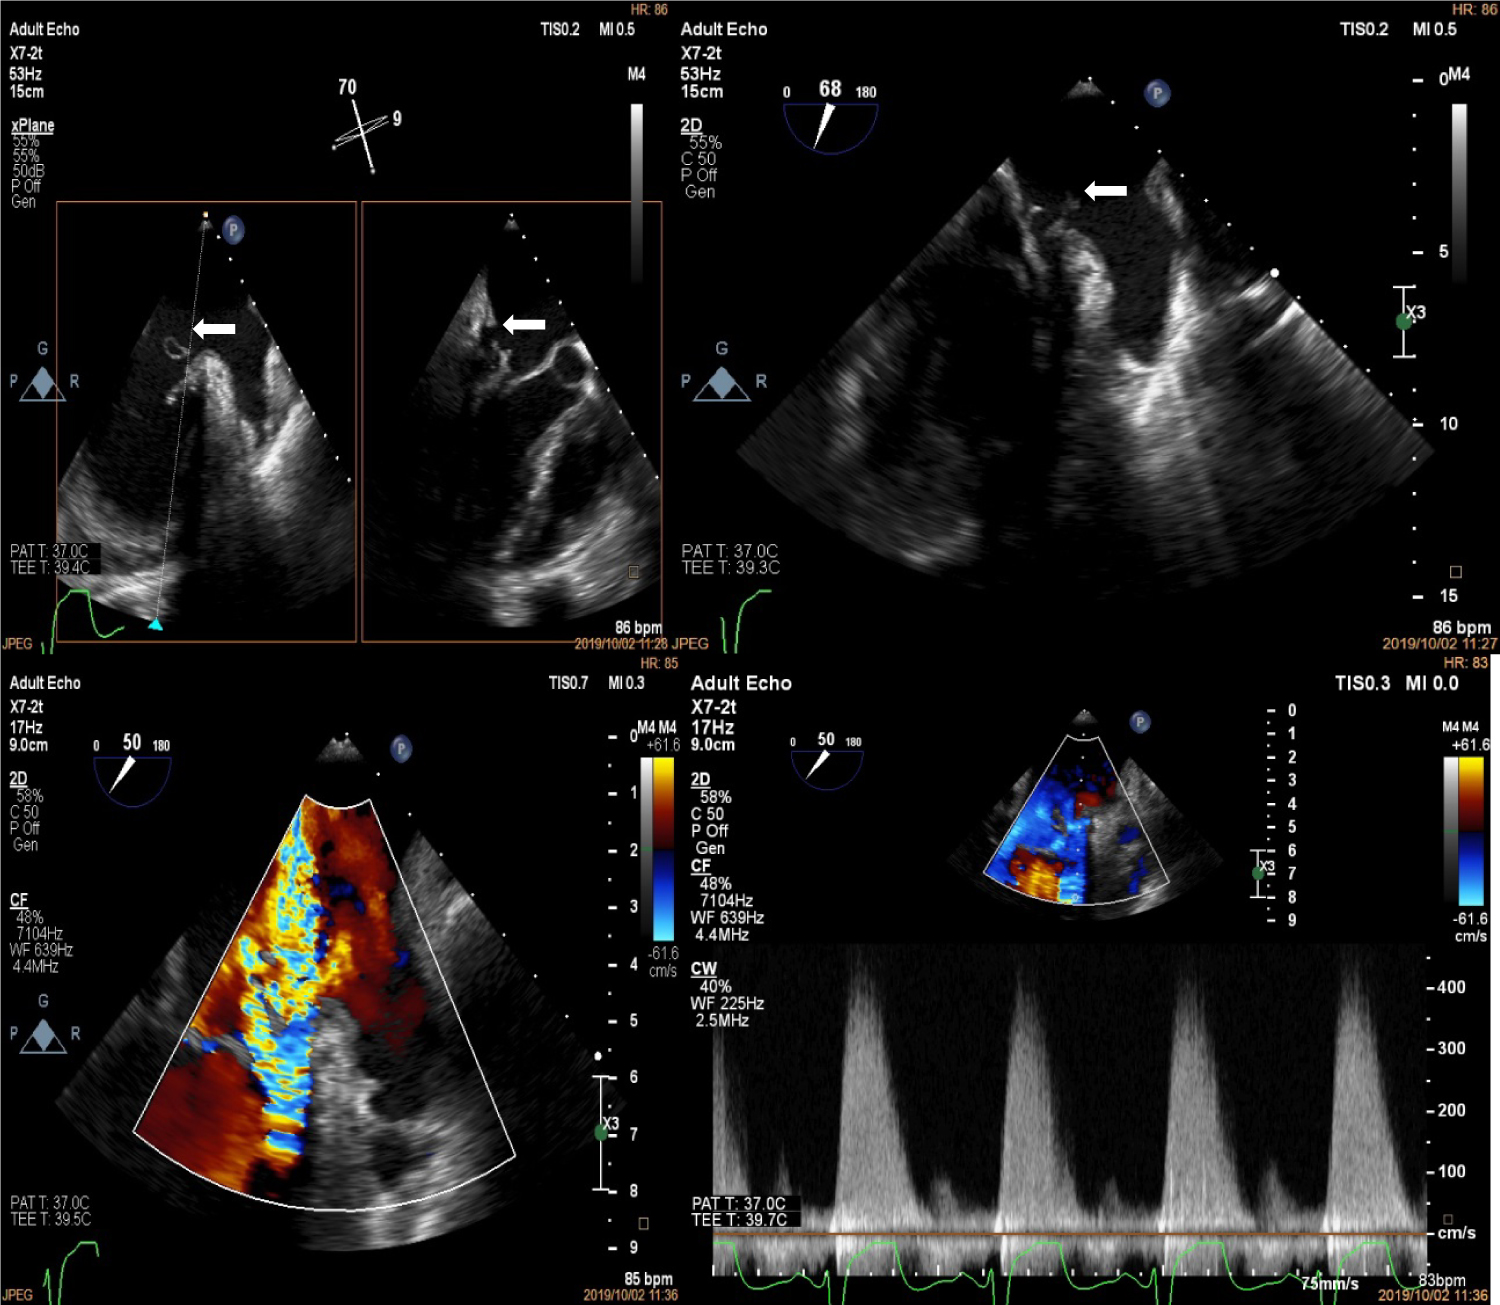

Upon arrival to the cardiology clinic, the patient was noted to be hemodynamically stable with a blood pressure of 126/83 mmHg and heart rate of 88 beats/min. He was not in heart failure. He had a displaced, volume overloaded apex beat and a grade 5/6 pan-systolic mitral regurgitation murmur. Twelve lead electrocardiograms showed sinus rhythm with wide P wave suggestive of left atrial enlargement and early repolarisation. His blood parameters revealed improved Haemoglobin at 11.1 g/dl, CRP of 37 mg/l and a normal urea and electrolytes. He underwent trans-thoracic echocardiography (TTE), which revealed a left ventricular end-diastolic diameter of 62 mm and left ventricular end- systolic diameter of 34.7 mm with an EF of 65%. Right ventricular systolic function was preserved with a trans-annular planar systolic excursion of 2.6 cm and RV S' velocity of 15.5 cm/s. There was severe eccentric mitral regurgitation and severe tricuspid regurgitation with an estimated pulmonary artery systolic pressure of 82 mmHg. No masses or vegetation's were noted. Two discrete aneurysms were noted, one just below the mitral annulus inferior to the posterior mitral leaflet (PML) and the second at the apex of the left ventricle (Figure 1). The patient subsequently underwent two dimensional and three- dimensional transoesophageal echocardiogram (TEE) which confirmed the presence of sub-mitral aneurysm and apical aneurysm. There was spontaneous echo contrast and thrombus in the sub-mitral aneurysm (Figure 2). The PML was perforated revealing two mitral regurgitation jets, one through the perforation and the second was central in origin (Figure 3 and Figure 4). There was also suspicion of oscillating mass on the PML (Figure 3). His blood cultures remained negative. The gene expert for Tuberculosis was negative. He tested negative for syphilis, Human immunodeficiency virus, connective tissue disease and sarcoidosis using the Treponema Haemagglutination test, HIV serology, antinuclear antibody test and serum angiotensin converting enzyme assays, respectively. The patient underwent Multi-detector Computed Tomography (MDCT) to define in detail the anatomical course of the aneurysms and also to exclude coronary artery disease. Multiple left ventricular aneurysms were noted in the posterior wall and the apex (Figure 5 and Figure 6). Aneurysm in the mid-postero-lateral wall measured 38.9 mm × 16.6 mm, sub-mitral aneurysm with thrombus in situ, measured 57.5 mm × 37.8 mm and it dipped inferior to the left atrium (Figure 6). The apical aneurysm in the inferior aspect was calcified at the antero-lateral margin and measured 54.4 mm × 12.7 mm, and in the septal aspect measured 26.9 mm × 14.7 mm. A discrete perforation was noted in the PML measuring 11.1 mm in diameter (Figure 5). There was no significant mediastinal lymphadenopathy.

Figure 2: Trans-oesophageal echocardiogram at the mid-oesophageal position showing spontaneous echo contrast and thrombus formation in the sub-mitral aneurysm (white arrows). View Figure 2

Figure 3: Trans-oesophageal echocardiogram at the mid-oesophageal level showing perforation of the P1 segment of the posterior mitral leaflet (top left, white arrows) with possible vegetation (top right, white arrows). The bottom panels show the severe mitral regurgitation jets on colour (left) and continuous wave Doppler (right). View Figure 3